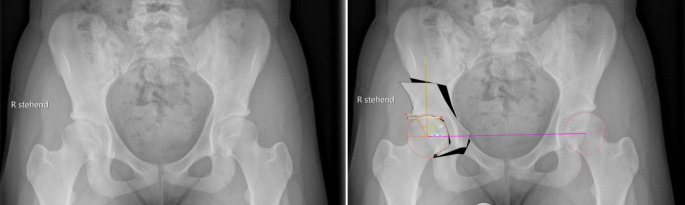

Vor der Operation ist die digitale Planung obligat, um das optimale Ausmaß der Korrektur zu bestimmen und eine postoperative Über- oder Unterkorrektur zu vermeiden. In der a.-p.-Beckenübersicht sind ein postoperativer LCE-Winkel von 30°, ein positiver Tragflächenwinkel (Norm zwischen 3 und 13°), ein Femurkopfextrusionsindex ≤ 27 % (Norm von 17° und 27°) und ein antevertiertes Azetabulum die Zielwerte für die Korrektur (Abb. 1). Die azetabuläre Version kann aktuell jedoch nicht mittels der Planungssoftware geplant werden. Diese sollte jedoch präoperativ evaluiert werden, und in diesem Zusammenhang sollten präoperativ der „acetabular wall index“ und Retroversionszeichen wie „cross-over sign“, „posterior wall sign“ und der „acetabular wall index“ erhoben werden.

In der vorliegenden Arbeit präsentieren wir die Ergebnisse der ersten 39 Patienten (36 Frauen und 3 Männer), die zwischen Januar 2016 und August 2017 vom Seniorautor operativ mittels oben genannter Technik versorgt wurden, zu einem mittleren Follow-up von 3,5 (3 bis 4,5) Jahren. Das durchschnittliche Alter zum Operationszeitpunkt betrug 23 (16 bis 42) Jahre, und der durchschnittliche Body Mass Index (BMI) lag bei 27 (18–36) kg/m2. Die durchschnittliche Operationsdauer betrug 88 (57 bis 142) Minuten. Bezüglich der radiologischen Parameter konnten der LCE-Winkel signifikant von präoperativ 16,1° (7–24°) auf postoperativ 30,5° (25–37°) (p < 0,0001) und der AC-Winkel signifikant von präoperativ 13,2° (2–25,3°) auf postoperativ 2,8° (−3–13°) (p < 0,0001) korrigiert werden.

In 20 von 39 Fällen (51,3 %) wurde eine Hypästhesie durch eine Schädigung des NCFL am lateralen Oberschenkel registriert. Neben der Verletzung des NCFL wurden keine weiteren Nervenverletzungen und keine Gefäßkomplikationen beobachtet. Bei keinem der Patienten war die Transfusion von Erythrozytenkonzentraten notwendig. Es zeigten sich keine ungewünschten intra-/postoperativen Frakturen, und es kam zu keinem postoperativen Korrekturverlust. Es kam in 3 Fällen (7,7 %) zu einer Über‑/Unterkorrektur der dreidimensionalen Korrektur. In einem Fall wurde das Azetabulum überkorrigiert mit einem LCE-Winkel von 37° und einem AC-Winkel von −3°. Bei 2 Patienten wurden postoperative azetabuläre Retroversionen registriert. Bei einem dieser Patienten wurde die präoperativ vorliegende Retroversion nicht ausreichend korrigiert. Bei dem zweiten Patienten zeigte sich postoperativ bis zum letzten Follow-up eine vermehrte postoperative Beckeninklination auf der a.-p.-Beckenübersichtsaufnahme. Dadurch entstand eine funktionelle Überkorrektur der anterioren Überdachung.